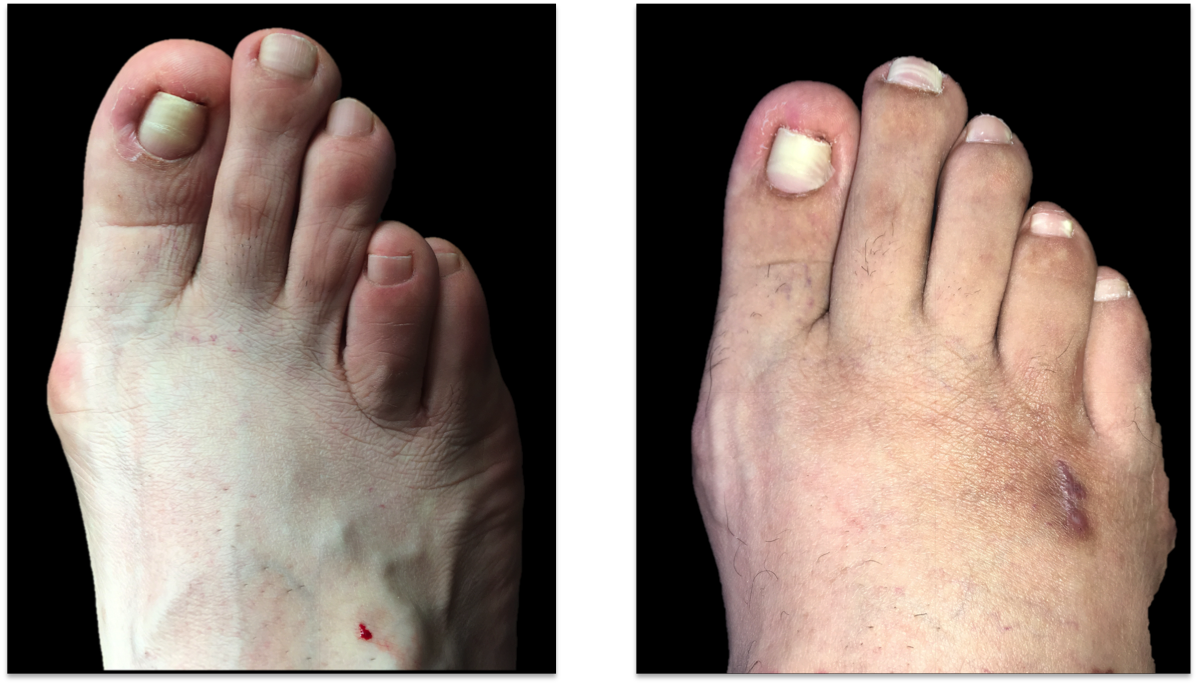

Below is a case of a 35 year old female who underwent two failed attempts at brachymetatarsia correction. She came to us for revision, we then performed a metatarsal lengthening with gradual correction that enabled us to fix the nonhealing bone from the last surgery and a skin procedure was done to help pull the toe down. the postoperative picture is on the right.